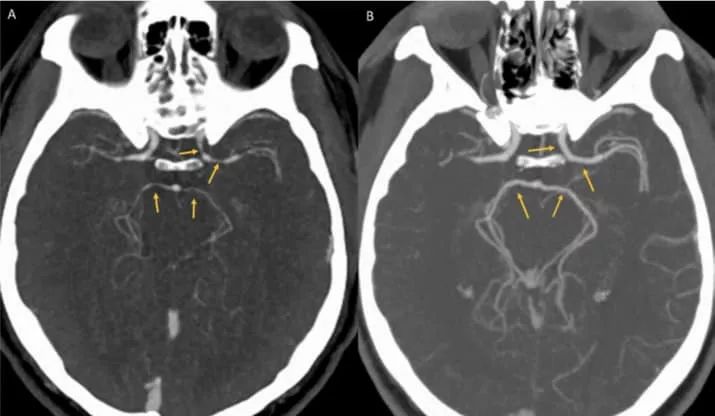

这种罕见的情况是由于大脑中主要的血管突然变窄引起的。医生为他做了脑部CT,影像显示该男子的大脑动脉变窄,这种情况被称为可逆性脑血管收缩综合征(RCVS),而RCVS的主要症状就是霹雳头疼

做完CT的影像。左侧影像箭头所指处,血管有明显狭窄。图片来源:casereports.bmj.com